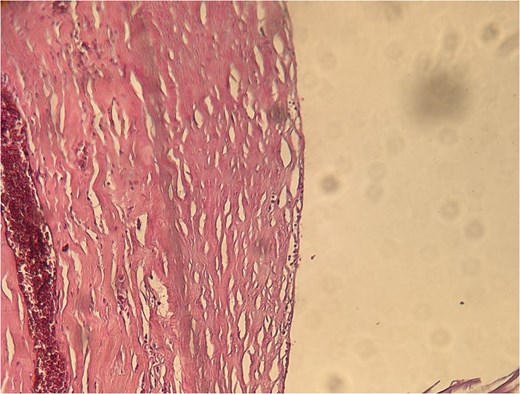

A 60-year-old Moroccan female with no significant medical history presented with chronic periumbilical pain lasting several months, without associated digestive or systemic symptoms, and preserved general condition. Clinical examination revealed periumbilical tenderness. Abdominal ultrasound was unremarkable, prompting an abdominopelvic CT scan, which identified a retroperitoneal inter-aortocaval cystic lesion measuring 86 mm. Surgical exploration revealed a large cystic mass in the mesentery of the small intestine, which was entirely excised. Histopathological examination showed variable-sized cystic cavities with a lymphatic appearance (Fig. 1), lined by flattened and regular endothelium. Some cavities contained pale eosinophilic material interspersed with lymphocytes and areas of red blood cells (Fig. 2). The interstitial tissue exhibited lymphocytic and plasmacytic inflammatory infiltrates. Immunohistochemistry confirmed the lymphatic nature with positivity for Podoplanin/D2–40 (Fig. 3) and CD34 (Fig. 4) and negativity for calretinin (Fig. 5). The patient’s postoperative course was uneventful.

Eosinophilic material and inflammatory infiltrates composed of lymphocytes and red blood cells.